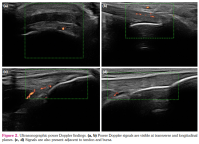

MASEI index evaluated five elemental lesions (scores) of enthesis: structure (0 or 1), thickness (0 or 1), erosions (0 or 3), calcifications (0, 1, 2, or 3), bursae (only at distal patellar tendon and Achilles tendon) (0 or 1), power Doppler signal (0 or 3).[22] Calcifications were scored as 0 if it was absent, 1 if <5 mm, 2 if 5-10 mm, or 3 if they were >10 mm.[23] Bursitis was defined as a compressible by the transducer, localized anechoic or hypoechoic, well-circumscribed area at Achilles enthesis and distal patellar enthesis. Erosion was defined as a cortical breakage with a step-down contour defect in two planes. A thickness assessment was made by measuring the maximal thickness at the bone insertion site. Based on enthesis-specific values (plantar aponeurosis >4.4 mm, Achilles tendon >5.29 mm, proximal and distal patellar tendon >4 mm, quadriceps tendon >6.1 mm, and triceps enthesis >4.3), it was determined whether there was an increase in thickness. Structural evaluation was defined as pathological in the presence of any of the loss of fibrillar pattern, hypoechoic appearance, and fusiform thickening in the enthesis area. The total score ranged from 0 to 136. The MASEI-Inflammatory score was recorded as entheseal thickness, structural changes, bursitis, and power Doppler findings, and MASEI-Damage score was recorded as calcifications and erosions (Figures 1, 2).[23]